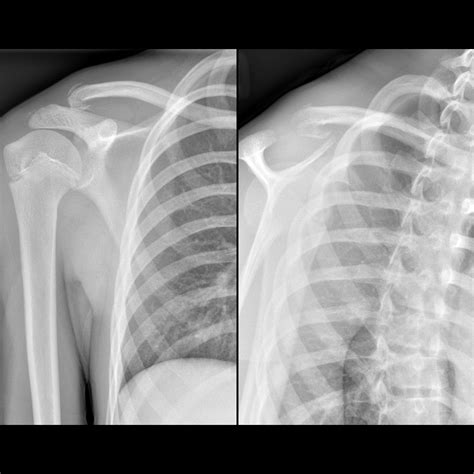

• X-rays: Often the first line of defense for bone fractures or lung issues.

X-ray Minimal Bone fractures, pneumonia, chest congestion